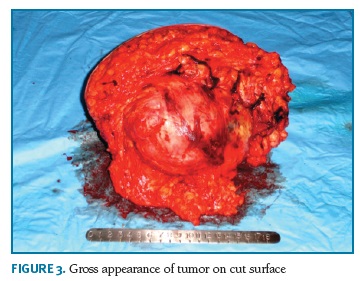

A 74-years-old woman, who has provided her written informed consent, caucasian, menopause at 50 years and was never treated with hormone replacement therapy or contraceptive pills, with past history of myocardial infarction, hypertension and obesity, in March 2007 noticed a tumor in the left breast with 4 cm in largest diameter. At that time, she recurred to Obstetrics and Gynecology Department in Cova da Beira University Hospital Center. Mammographic findings suggested benignity of the lesion (Fig. 1) and a biopsy was performed. Pathologic diagnosis was not definite, suggesting the diagnosis of fibroadenoma or phylloides tumor. The patient refused any further biopsy or surgical treatment. In November 2007, she returned to the same Department with a large 20 cm breast tumor (Fig. 2). A new breast core-biopsy was performed and a pathologic diagnosis of malignancy was excluded. Then, the patient accepted left total mastectomy as the best treatment (Fig. 3).

Definitive pathologic diagnosis of Pseudoangiomatous Stromal Hyperplasia (Fig. 4-5-6-7-8) was made on surgical specimen of mastectomy. The patient had regular follow-up at our department. Last visit was in May 2018, and no signs recurrence or contralateral breast cancer were diagnosed in those 11 years of follow-up.